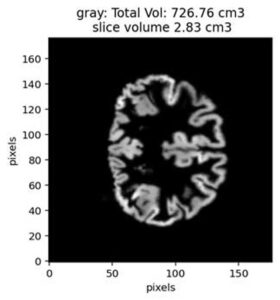

My research integrates advanced neurophysiological and microscopic techniques, with histology and cutting-edge signal processing analysis to explore the fundamental aspects of brain function under health and disease. I focus on cellular communication and network dynamics and interrogate the interplay between intrinsic ionic mechanisms, synaptic transmission and native glial dynamics in relation to physiological and pathophysiological states in neurodegenerative disorders such as multiple sclerosis, Parkinson’s and Alzheimer’s Disease.